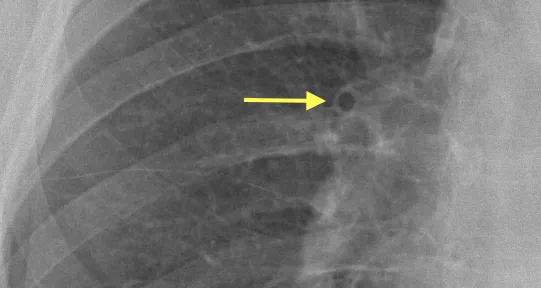

Kerley C lines: Expansion of the interstitial space by fluid.

<b>Kerley </b><b>C lines:</b> Expansion of the interstitial space by fluid.</p>